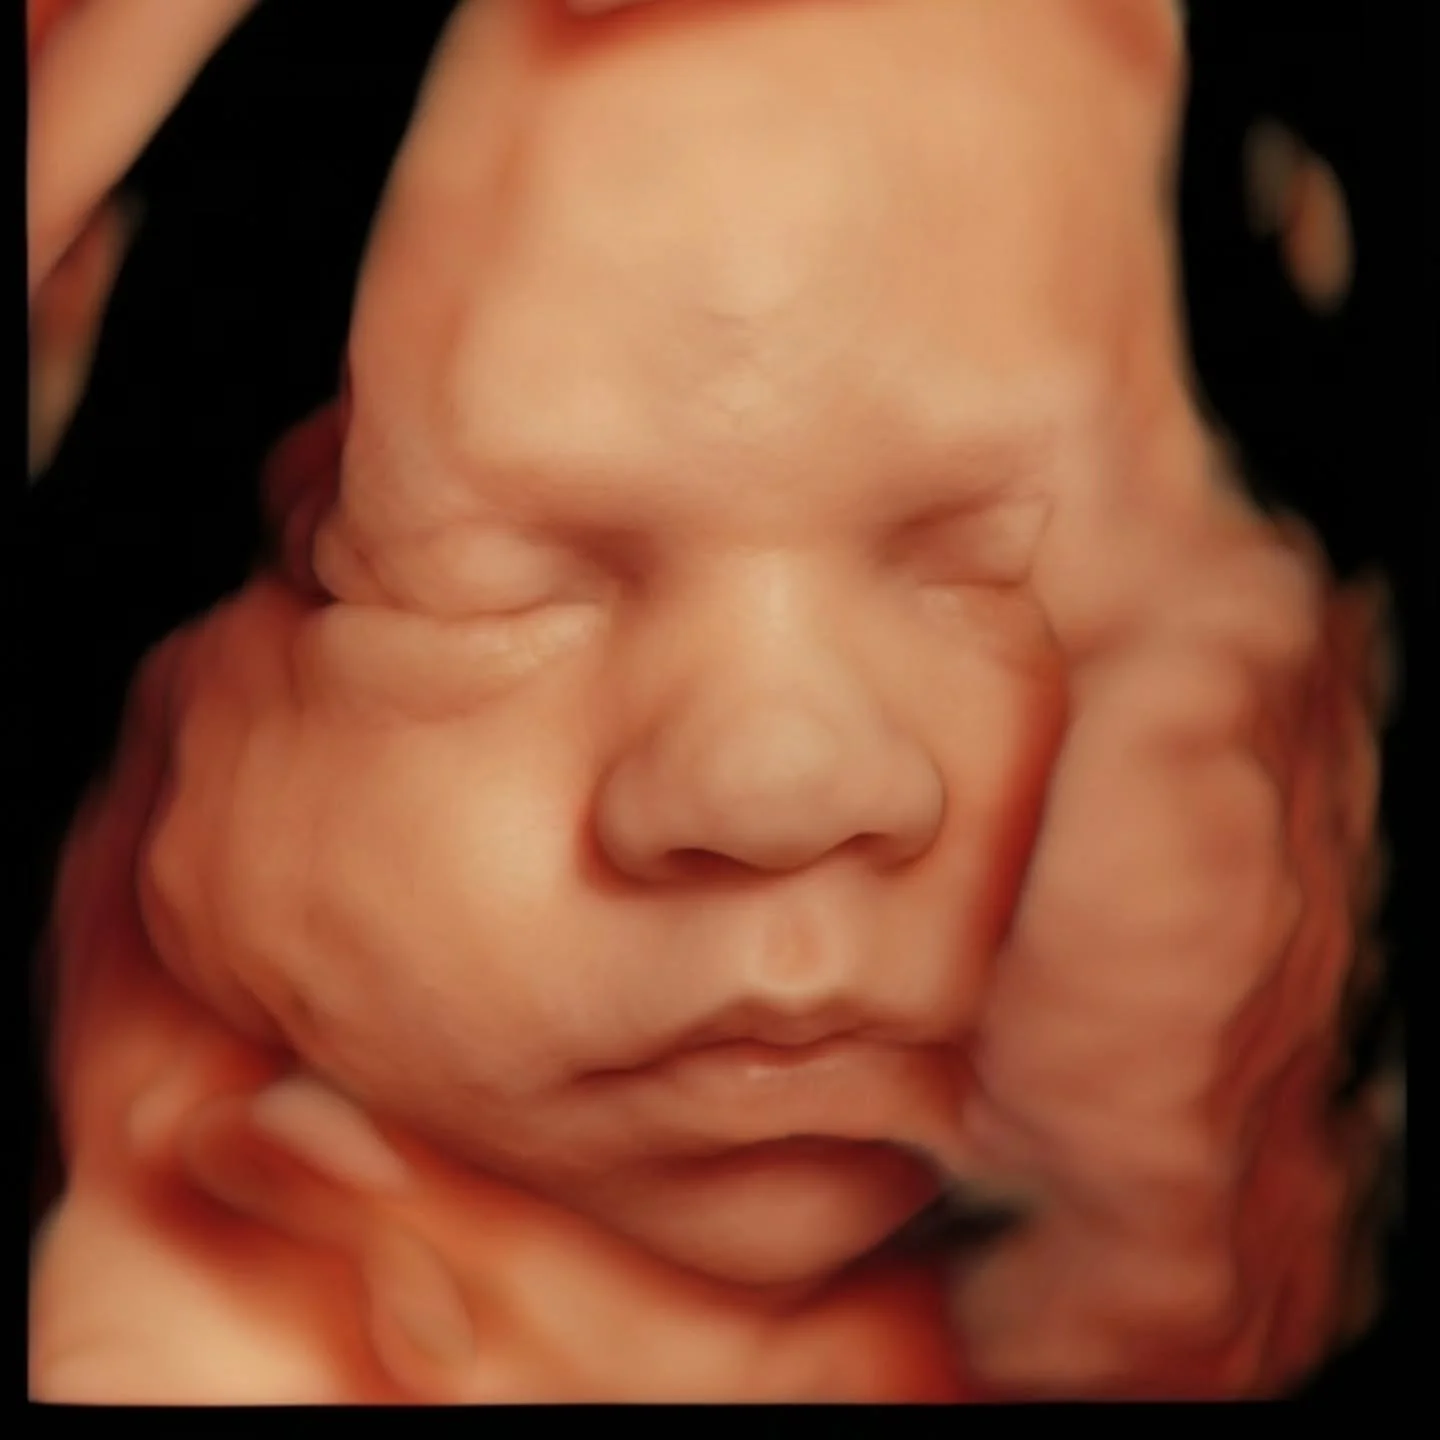

Our state of the art technology allows us to see your baby in a whole different way! With HD Live imaging, we can watch your baby wiggle, smile and yawn all in real time!

With over 14 years of experience as a Registered Sonographer, Life in Bloom Sonography Studio was created with one clear intention: to offer families more than an ultrasound — an experience rooted in care, expertise, and connection.

Every session is guided by advanced training, a deep understanding of fetal imaging, and a genuine passion for creating meaningful moments for growing families. From the first scan to the final keepsake, each detail is handled with precision, patience, and heart.